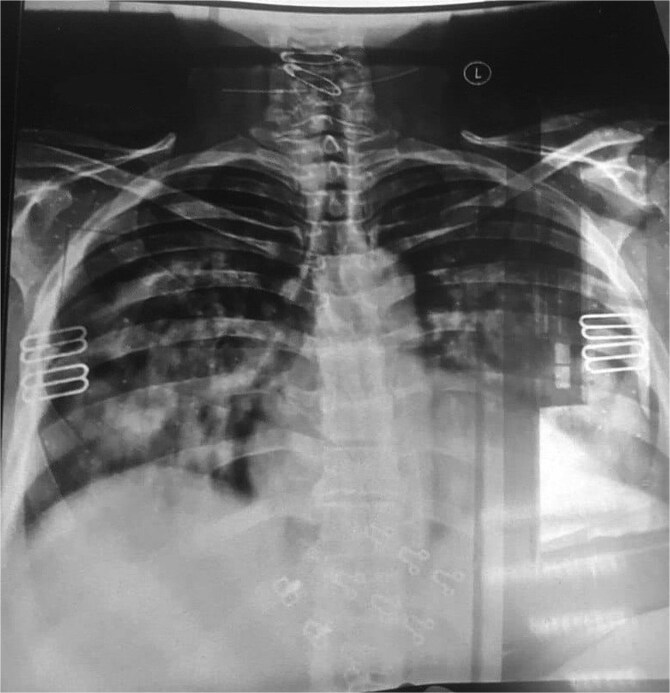

系统性红斑狼疮(SLE)是一种自身免疫性全身性疾病,由于其广泛的临床表现影响多个器官,因此对诊断提出了挑战。特别罕见的是弥漫性肺泡出血(DAH),这是一种由毛细血管-肺泡屏障破坏引起的严重并发症,可迅速发展为危及生命的疾病。我们报告一例57岁的女性谁提出到急诊科经历呼吸困难和咯血。她的初步评估显示贫血和血小板减少,高分辨率计算机断层扫描显示弥漫性双侧浸润,表明DAH。这些发现导致了先前未被识别的SLE的诊断。该病例强调了在鉴别诊断DAH时考虑SLE的重要性,强调了及时诊断和积极治疗的必要性,以改善患者的预后。

Systemic lupus erythematosus (SLE) is an autoimmune systemic disease that presents a diagnostic challenge due to a wide range of clinical manifestations affecting multiple organs. Particularly rare is its presentation with diffuse alveolar hemorrhage (DAH), a severe complication that arises from the disruption of the capillary-alveolar barrier and can rapidly progress to a life-threatening condition. We report a case of a 57-year-old female who presented to the emergency department experiencing dyspnea and hemoptysis. Her initial evaluations revealed anemia and thrombocytopenia, with high-resolution computed tomography scans showing diffuse bilateral infiltrates indicative of DAH. The findings led to the diagnosis of previously unrecognized SLE. This case underscores the importance of considering SLE in the differential diagnosis of DAH, emphasizing the necessity for prompt diagnostic workup and aggressive treatment in such critical presentations to improve patient outcomes.